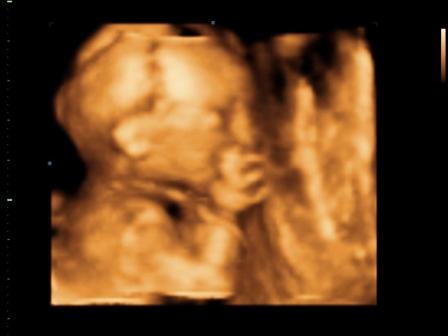

Mamacka neked nagyon profi képeket csináltak, főleg az arcáról! Koutchnak pedig a fütyiről! :)

Azért nem olyan profi... tök béna volt a nőci... sokkal szebbeket lehetett volna. Férjem már majdnem kivette a kezéből, hogy inkább majd ő csinálja! :) :lol: :lol: :lol: :lol: :lol: :lol: :lol: :roll:

mi is megjöttünk, minden ok. nagyon szégyenlős volt, szinte semmit nem mutatott az arcából. a placentát, mint egy kismama a szopipárnát ölelte, és jól odabújt. amúgy egészséges, pöckét mutogatta, így nekünk is tuti a fiú. auszrtál volt az uhás nő, jófej volt, alapos.

CD-t én is kaptam, képeket minnyá nézek róla. Ja, a képek nálam se lettek nagyon jók, mert ő is belefúrta magát a lepénybe. Ettől függetlenül szépen látszott, ahogy integet, kalimpál, fogja a fejét stb.

Jó volt, sokáig nézték a babócát, egy nagyon profi géppel, ahol mindenféle áramlást is vizsgáltak (pl.: főerek, köldökzsinórban lévő áramlást-itt még hang is volt, nagyon érdekes volt). Megnézték még egyszer a nemét is, és 100%, hogy kisfiú! Sokat mosolygót a baby, de végére elfáradt, és bújt el a kezei mögé, nagyon cuki volt!